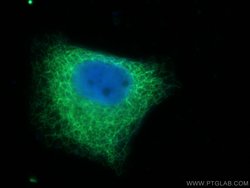

This antibody is specifically against KRT7.

| Immunocytochemistry, Immunofluorescence, Immunohistochemistry (Paraffin), Immunoprecipitation, Western Blot | |